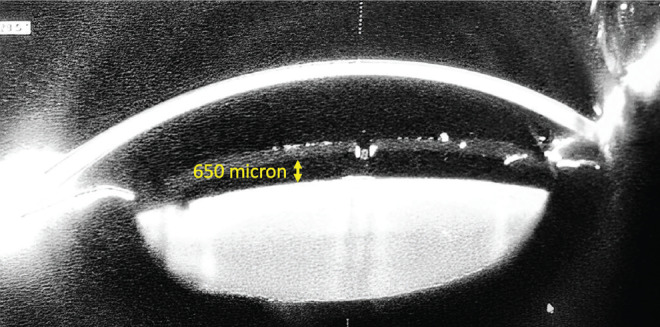

Urrets-Zavalia Syndrome After Posterior Chamber Phakic Intraocular Lens Implantation: An Unusual Complication.